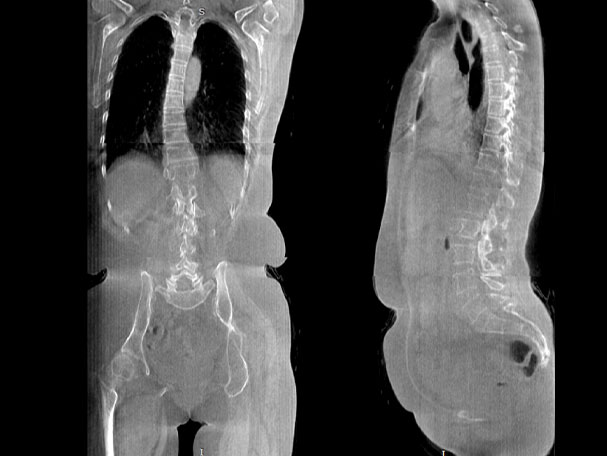

关闭金属伪影校正

开启金属伪影校正